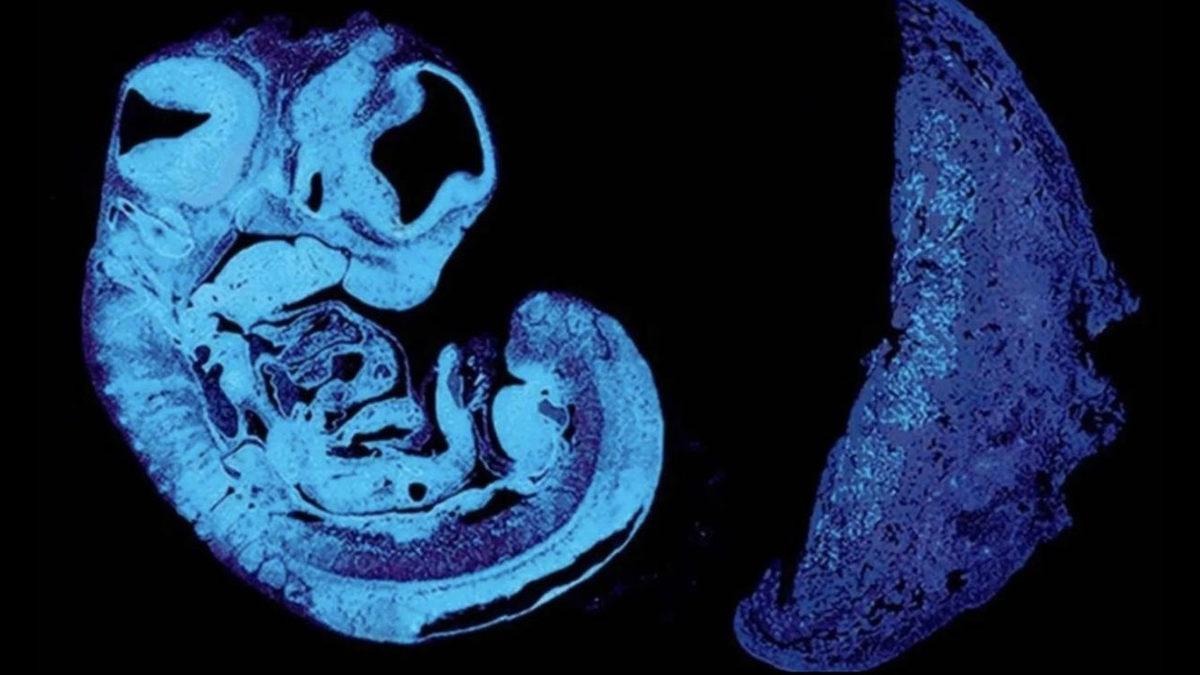

Birleşik Krallık’taki Cambridge Üniversitesi’nden bilim insanları, fareler üzerinde yürüttükleri yeni araştırmayla bazı bebeklerin rahimdeyken neden yetersiz büyüdüğünü araştırıyordu. Dünya çapında bebeklerin %10 – 15’inde görülen bu durum araştırılırken, bu duruma neden olan garip bir savaş keşfedildi.

Bebeklerin rahimde yetersiz gelişmeleri sonucunda genellikle plasentadaki kan damarlarının genişlemesinde de azalma görülüyor. Bu kan damarları, normalde gebeliğin orta ve geç dönemleri arasında genişleme yoluna gitmiyor. Bilim insanları da araştırmalarında fetüsün plasenta içindeki kan damarlarının büyümesini teşvik etmek için ürettiği bir sinyali, genetiği değiştirilmiş farelerde inceledi.